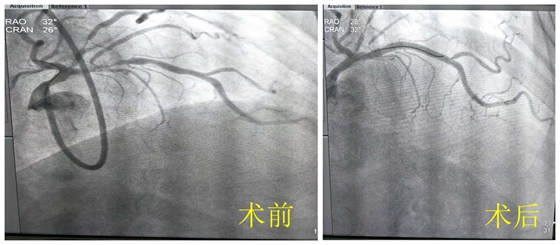

冠状动脉造影术前术后对比

完善术前准备后,我院特邀湖南省人民医院潘宏伟教授,与彭道地主任、范爱德主任医师携手,带领放射介入团队在IVUS(又称冠脉第三只眼)辅助下,行冠状动脉旋磨术。旋磨成功以后,采用球囊预扩张,然后植入药物洗脱支架覆盖病变。手术治疗过程顺利,未出现并发症。术后复查造影示支架贴壁良好,支架内无狭窄,远端血流正常,手术顺利完成,患者目前恢复良好。